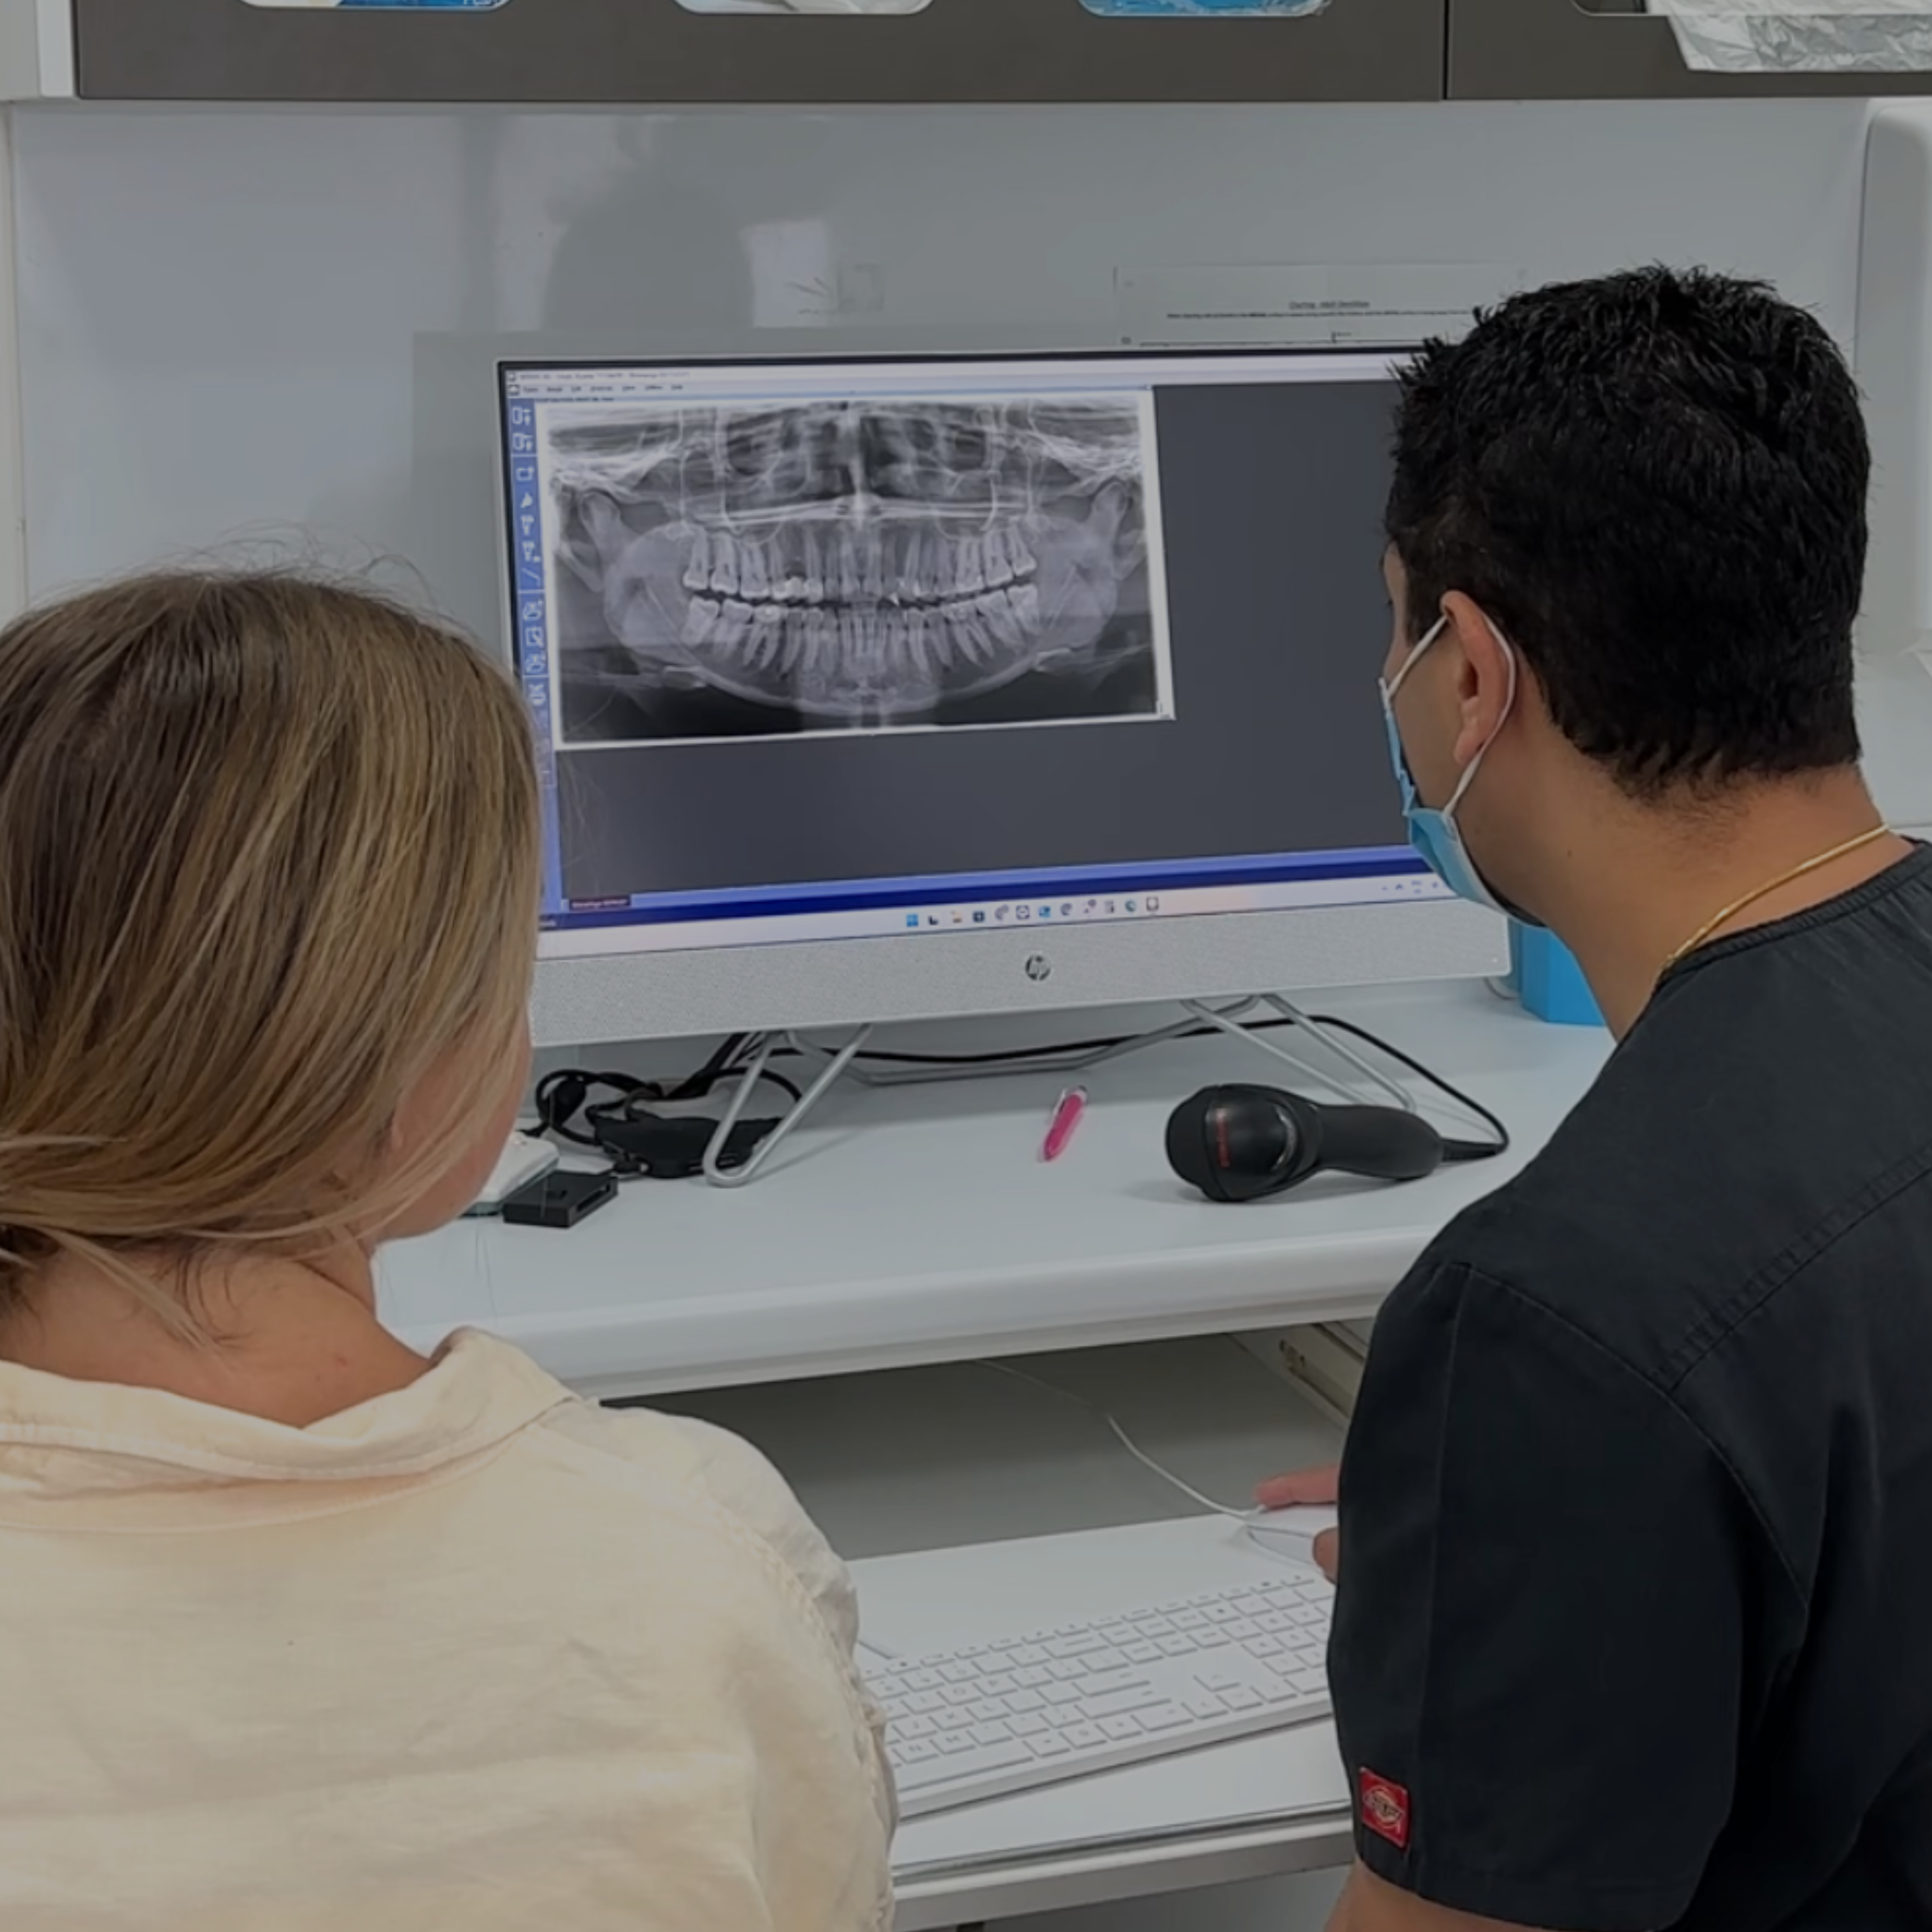

Start from home or in-clinic — either way, we’ll capture precise 3D data of your teeth to design a treatment plan that actually works. Every plan is crafted by Australian dentists for results you can trust.

Personalised Assessment

Your journey kicks off with a quick online assessment to figure out the best way forward. Whether you’d rather start from home or in-clinic, we’ll tailor your treatment plan to suit your goals — and keep things simple from the start.

At-Home: Order an Impression Kit to take accurate moulds and diagnostic images from home — reviewed by Australian dentists.

In-Clinic: Visit a bitesoftPro dentist for a 3D scan, and a face-to-face consult.

Good Oral Health

Candidates for clear aligners should have healthy teeth and gums, free from untreated cavities or active gum disease. Before starting treatment, it’s important to have a dental check-up to ensure there are no underlying oral health concerns that need addressing.